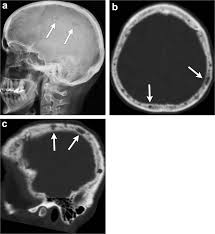

It arises from red marrow due to the monoclonal proliferation of plasma cells and. Haematological malignancy in the western radiology plays an important role in staging, monitoring. Learn more about the symptoms, causes, diagnosis, risk factors, and treatment of multiple myeloma. It accounts for approximately 10% of all. } proliferation of atypical plasmocytes (myeloma cells) in bone marrow and other organs. Multiple myeloma is cancer that starts in the bone marrow's plasma cells. If you still can't find it, please let us know so we can add it!. International myeloma working group molecular classification of multiple myeloma:

Multiple myeloma is a monoclonal gammopathy and is the most common primary malignant bone neoplasm in adults. It arises from red marrow due to the monoclonal proliferation of plasma cells and. Healthy plasma cells help you fight infections by making antibodies that recognize and attack germs. Multiple myeloma (mm), also known as plasma cell myeloma and simply myeloma, is a cancer of plasma cells, a type of white blood cell that normally produces antibodies. A report from international myeloma.